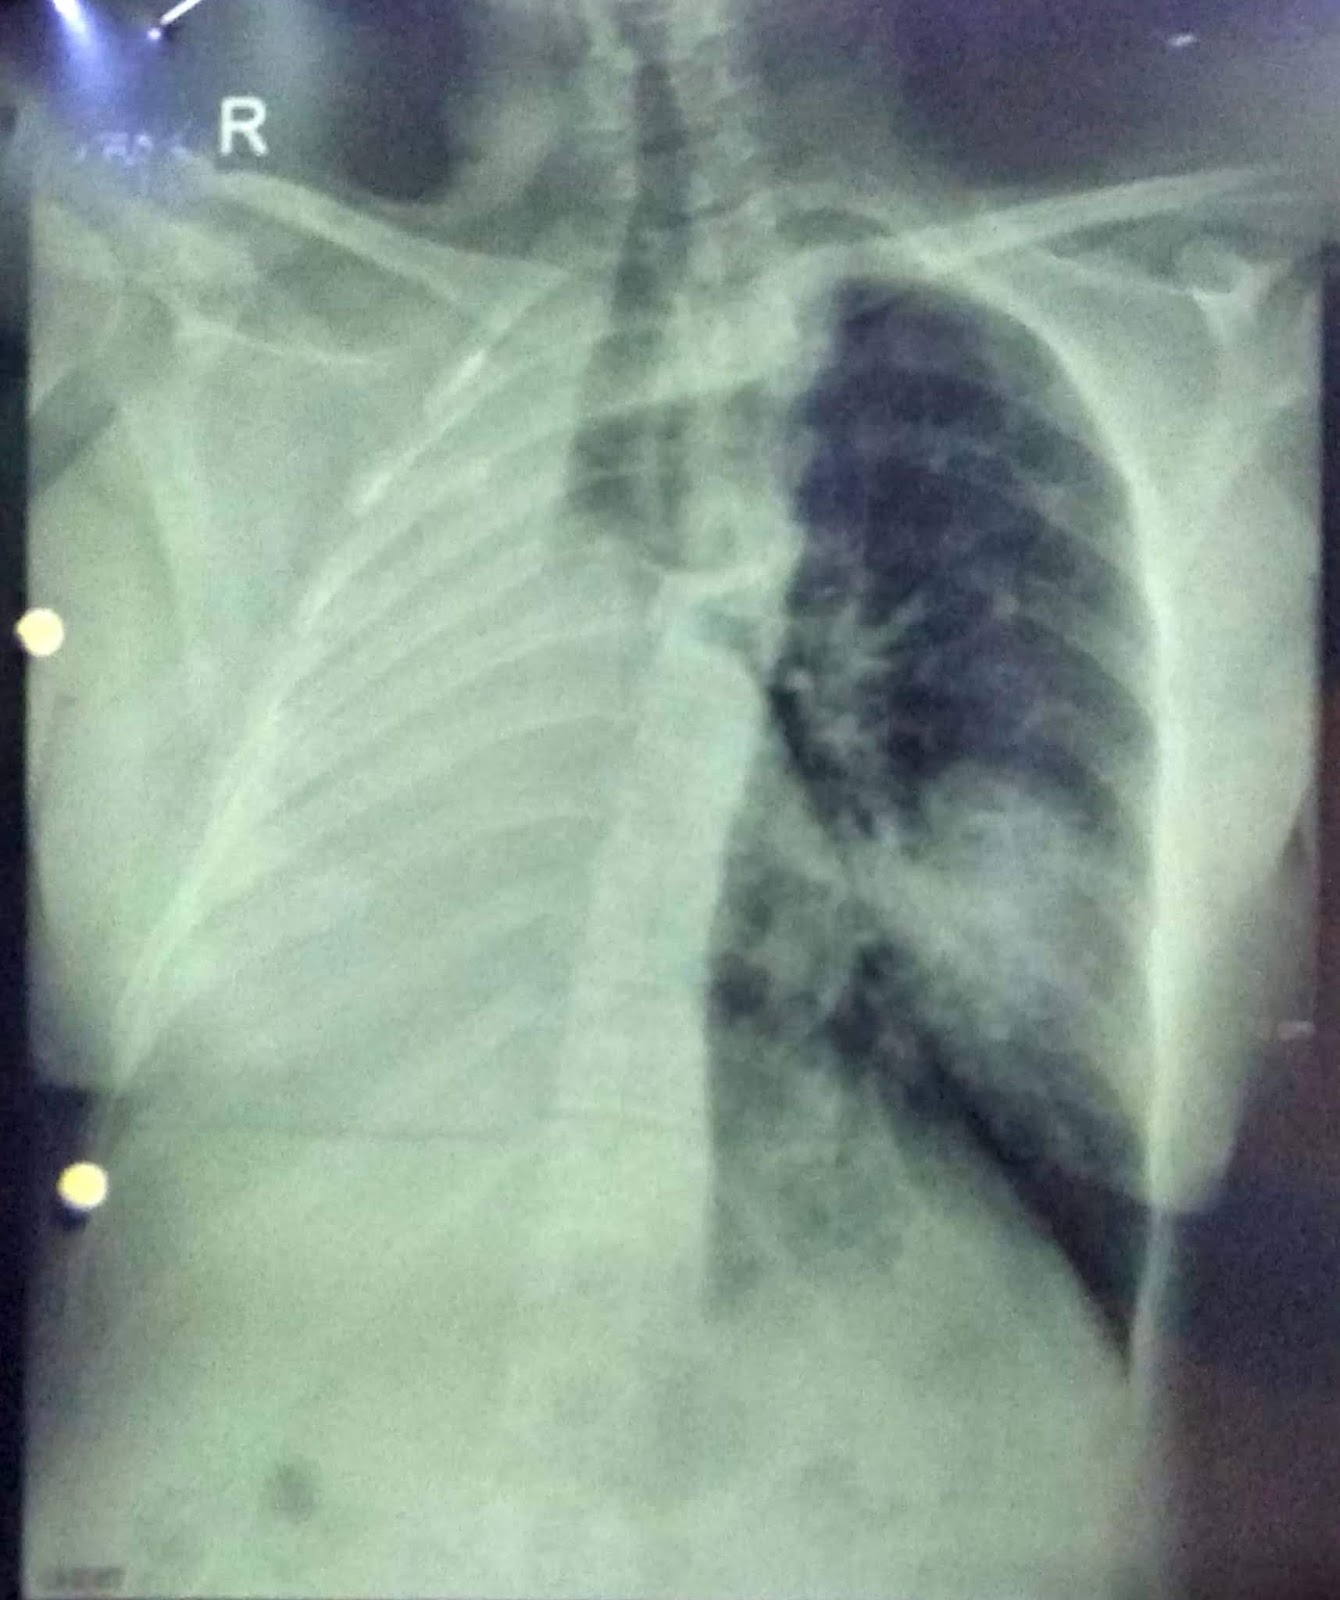

The appearance of lung metastasis in patient that was reported. Download Scientific Diagram Chest X Ray Molar Pregnancy a molar pregnancy occurs when an egg and sperm join incorrectly at fertilization and create a noncancerous. a health care provider who suspects a molar pregnancy is likely to order blood tests and an ultrasound. The level of human chorionic. There are 2 types of. one of the most important considerations is recognition of the possibility of. Chest X Ray Molar Pregnancy.

Gestational trophoblastic neoplasia chest x ray wikidoc Chest X Ray Molar Pregnancy There are 2 types of. the most common form of gtd is hydatidiform mole, also known as molar pregnancy. The level of human chorionic. a molar pregnancy occurs when an egg and sperm join incorrectly at fertilization and create a noncancerous. a health care provider who suspects a molar pregnancy is likely to order blood tests and. Chest X Ray Molar Pregnancy.